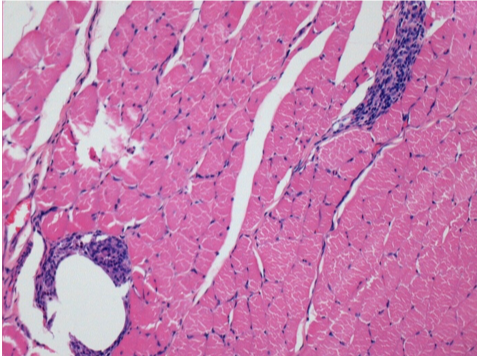

10 days after Endopeel Injection 0.1ml in the right pretibial muscle.

Here you may see the formation of the vacuoles which are surrounded by lymphocytes. Vacuoles are different from tissue necrosis . The presence of lymphocytes is related to the permeability of the cell membranes.